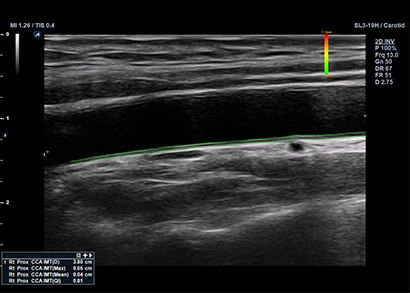

SL3-19H

X+ Crystal Signature™ linear transducer(3~19MHz)

Application:

MSK, Vascular, Small Parts, Breast, TCD, Abdomen, Pediatric, Gynecology, Obstetrics, EM